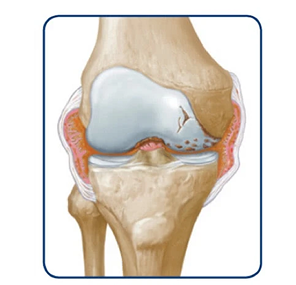

Joint bleeds—also called hemarthrosis—can happen when a joint is stressed. Repeated bleeds in the same joint may lead to chronic synovitis, where the joint lining becomes swollen and thick. Over time, this can limit movement and cause lasting joint damage.

The joint swells

If bleeds continue, it can degrade the cartilage and bone within the joint.

Over time, the joint may swell, change shape, and lose mobility.

Swelling of tissues in the knee may become permanent

Over time, this can lead to wearing away of the bone